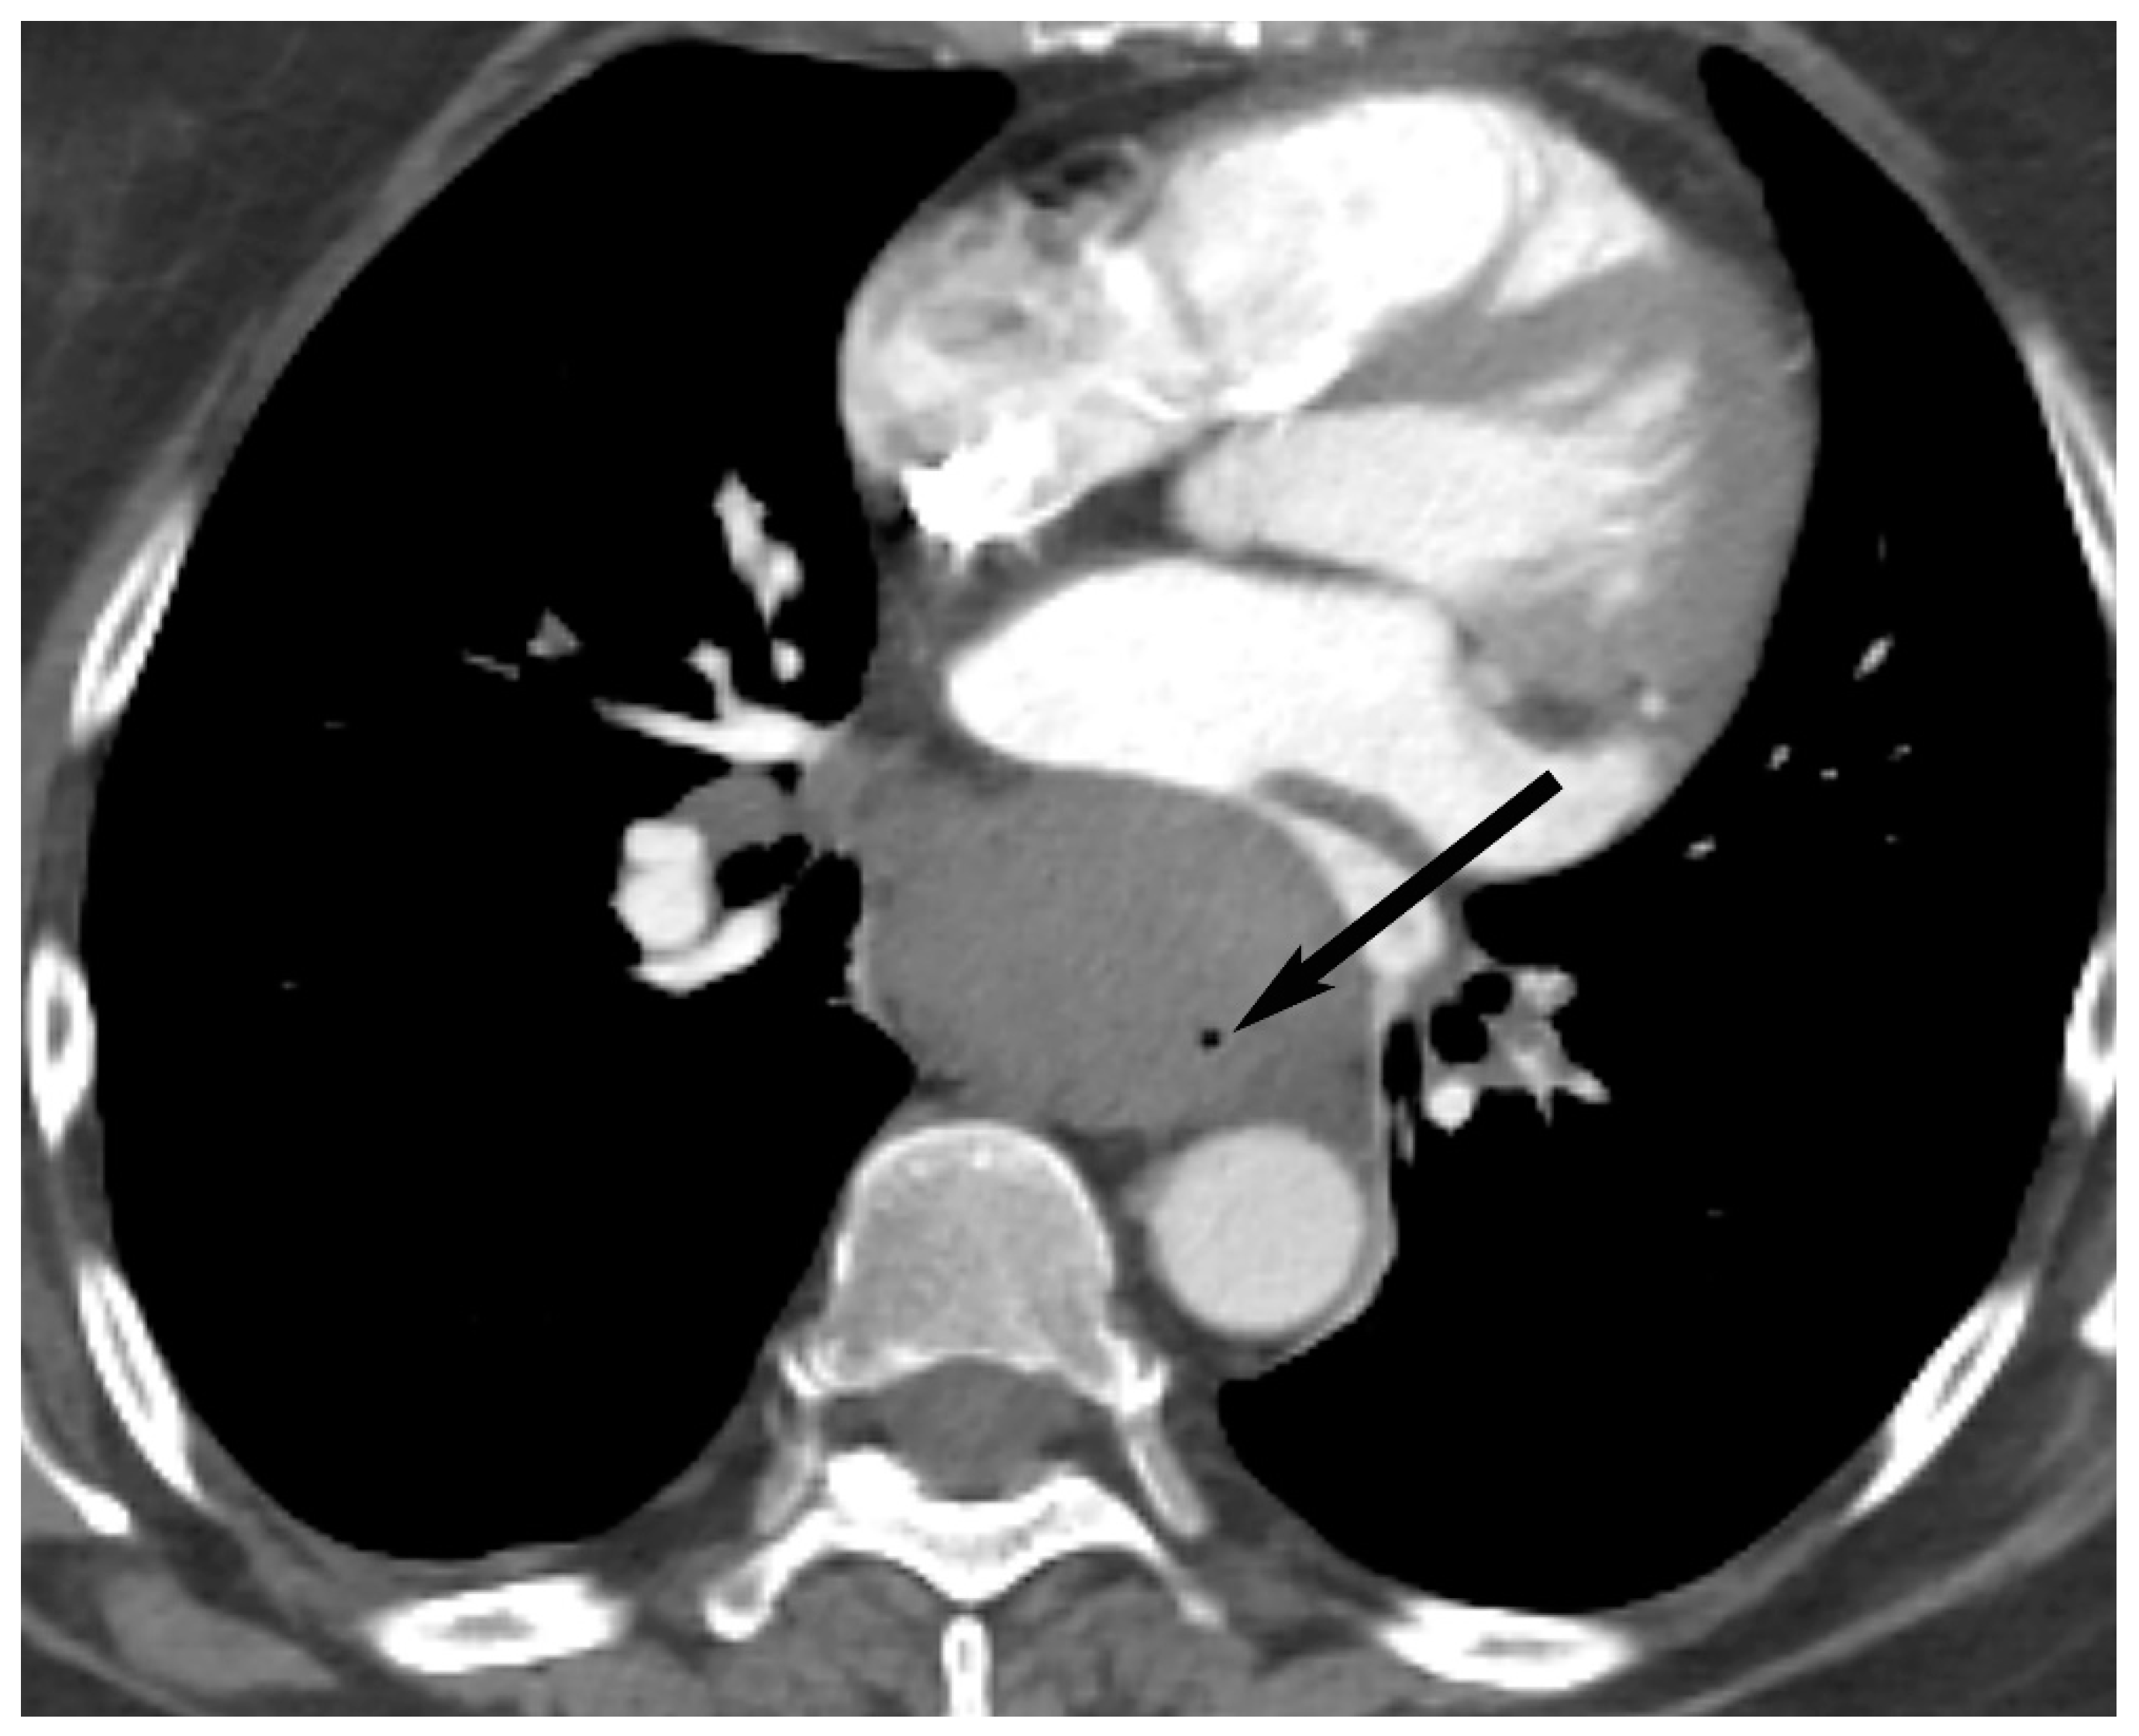

6. Lymphoma

8. Cystic Lesions